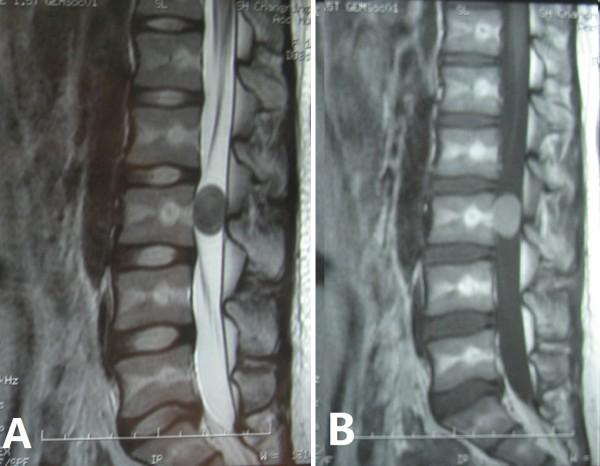

6例腰椎硬脊膜内表皮样囊肿患者的手术及预后情况

Surgery and outcomes of six patients with intradural epidermoid cysts in the lumbar spine.

The aim of this study was to analyze the clinical characteristics and discuss the treatment options for epidermoid cysts in the lumbar spine.

Epidermoid cysts are rare benign neoplasms, which account for less than 1% of all intraspinal tumors. Due to their rarity, there are only a few case reports in the literature. Complete excision is the recommended treatment for an epidermoid cyst, but this is difficult to achieve in the spine. In spite of their benign nature, local recurrence is not uncommon for spinal epidermoid cysts after incomplete excision.

Six patients with an epidermoid cyst in the lumbar spine underwent surgical treatment in our center between 2004 and 2011. A total excision using microsurgical techniques and reconstruction was successfully undertaken in all patients. Clinical data and detailed pathologic results were retrospectively analyzed. All cases were followed up for a median time of more than 4 years. The clinical data and surgical efficacy were analyzed to suggest treatment options for epidermoid cysts in the lumbar spine on the basis of a literature review and our own experience.

The mean age of the patients in this study was 37.7 years and the mean duration of pre-operative symptoms was 29.7 months (2 to 120 months). All patients were disease-free during their follow-up period. Radicular pain nearly disappeared, and patients suffering from neurologic deficits and defecation disorders recovered well.

Although an epidermoid cyst is a benign tumor, it is apt to recur locally following inadequate removal. Therefore, complete excision with preservation of neural function is an ideal protocol for intraspinal epidermoid cysts. Microsurgical techniques are very useful.